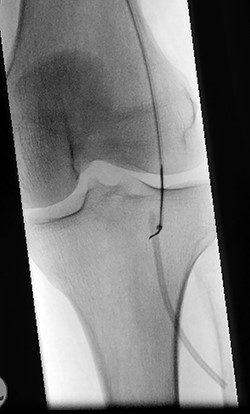

A 61-year-old male patient was diagnosed with inoperable stomach cancer. A TIVAD of the type Braun Celsite ST301® was inserted in the right subclavian vein for administration of chemotherapy. Location was confirmed by chest X-ray and the TIVAD was reported functioning with good backflow (Fig. 1). During initiation of the chemotherapy treatment, the TIVAD was reported malfunctioning. Contrast X-ray showed fibrin sheaths at the distal end of the catheter. An endovascular procedure was performed by an interventional radiologist and fibrin sheaths were mechanically removed with a snare (Fig. 2). Intraoperative X-ray with contrast showed normal contrast accumulation distal to the catheter tip and the patient received the first dose of chemotherapy. One month later the patient was hospitalized with bilateral pulmonary thromboembolism. The patient was treated with low-molecular-weight-heparin and discharged. The chemotherapy treatment continued as scheduled, with one pause due to a fracture of the right humerus after a fall. Occasionally, the TIVAD was malfunctioning and medication was administered using a peripheral venous catheter. During a planned pause in treatment, the patient sought hospital care due to worsening of his general condition. CT showed progress of malignancy and another round of chemotherapy was initiated and administrated using the TIVAD without any problems. Less than a week after, the patient reported feeling a tender swelling underneath his left foot. Ultrasound showed no DVT. The swelling and tenderness disappeared spontaneously, but the patient reported brief incidents of pain under his left foot. A CT scan was performed the next time the TIVAD did not function, showing that the distal 8 cm of the catheter was missing. The patient had no symptoms and reported no discomfort of any kind. The TIVAD was removed, confirming a fracture. A chest CT showed no foreign bodies. A full-body CT scan without contrast was performed, revealing the missing catheter part located at the level of the left knee (Figs 3 and 4). Vascular surgeons performed an endovascular procedure through the femoral vein assuming the catheter had embolized to the popliteal vein. Contrast examination revealed no catheter in the vein and another approach through the femoral artery was made, where contrast imaging shows that the catheter was, in fact, located in the popliteal artery (Fig. 5). The catheter, measuring 7.5 cm, was successfully removed with the use of a snare without any complications. The patient was discharged from hospital and referred to a diagnostic echocardiogram (Fig. 6). A bubble echocardiogram was performed to detect an atrial septal defect but was unsuccessful in doing so. For a final diagnosis, the patient was recommended a transesophageal echocardiogram, but as the diagnosis would not alter the course of treatment, the patient declined further examinations. Except for the reported episodes of pain and swelling of the left foot, the patient suffered no injury and finished his chemotherapy treatment.

Perioperative image of percutaneous removal of the catheter using a snare.